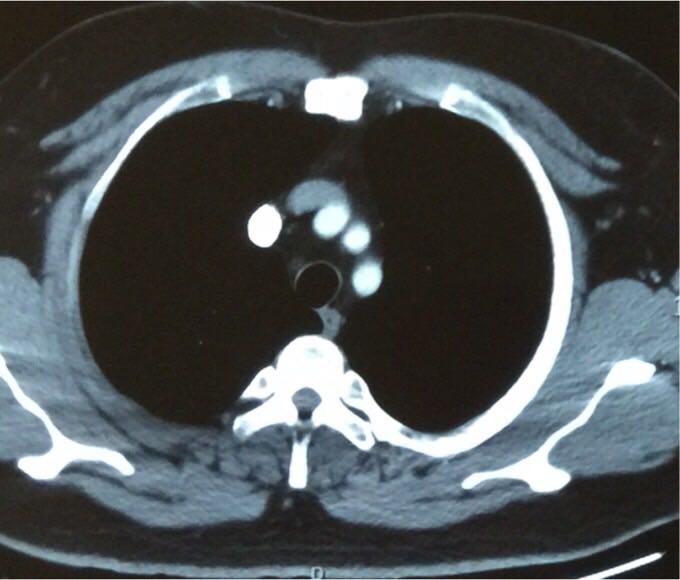

青年男性,无不适症状,体检发现前上纵膈一占位,CT见该肿物位于上腔静脉与主动脉之间,与周围组织分界较清,密度较为均匀,CT值约45HU左右。增强后轻度强化。患者无重症肌无力相关症状,考虑什么?